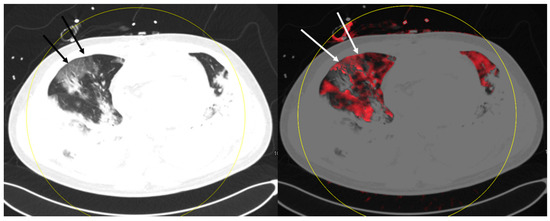

Dual-Energy Computed Tomography of the Lung in COVID-19 Patients: Mismatch of Perfusion Defects and Pulmonary Opacities